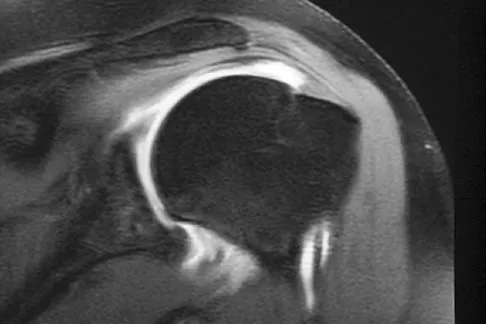

Figures 4a through 4c show the radiographs, CT scans, and T1-weighted MRI scan of a 19-year old man who has had increasing right hip pain and decreasing range of motion for the past several years. He also reports intermittent "locking" of the hip. What is the most likely diagnosis?

A 53-year-old man has had a long history of multiple joint symptoms, and he notes that the worst pain is from his left shoulder. A radiograph and MRI scan are shown in Figures 13a and 13b. Prior to surgical treatment of the shoulder, what is the most appropriate work-up?